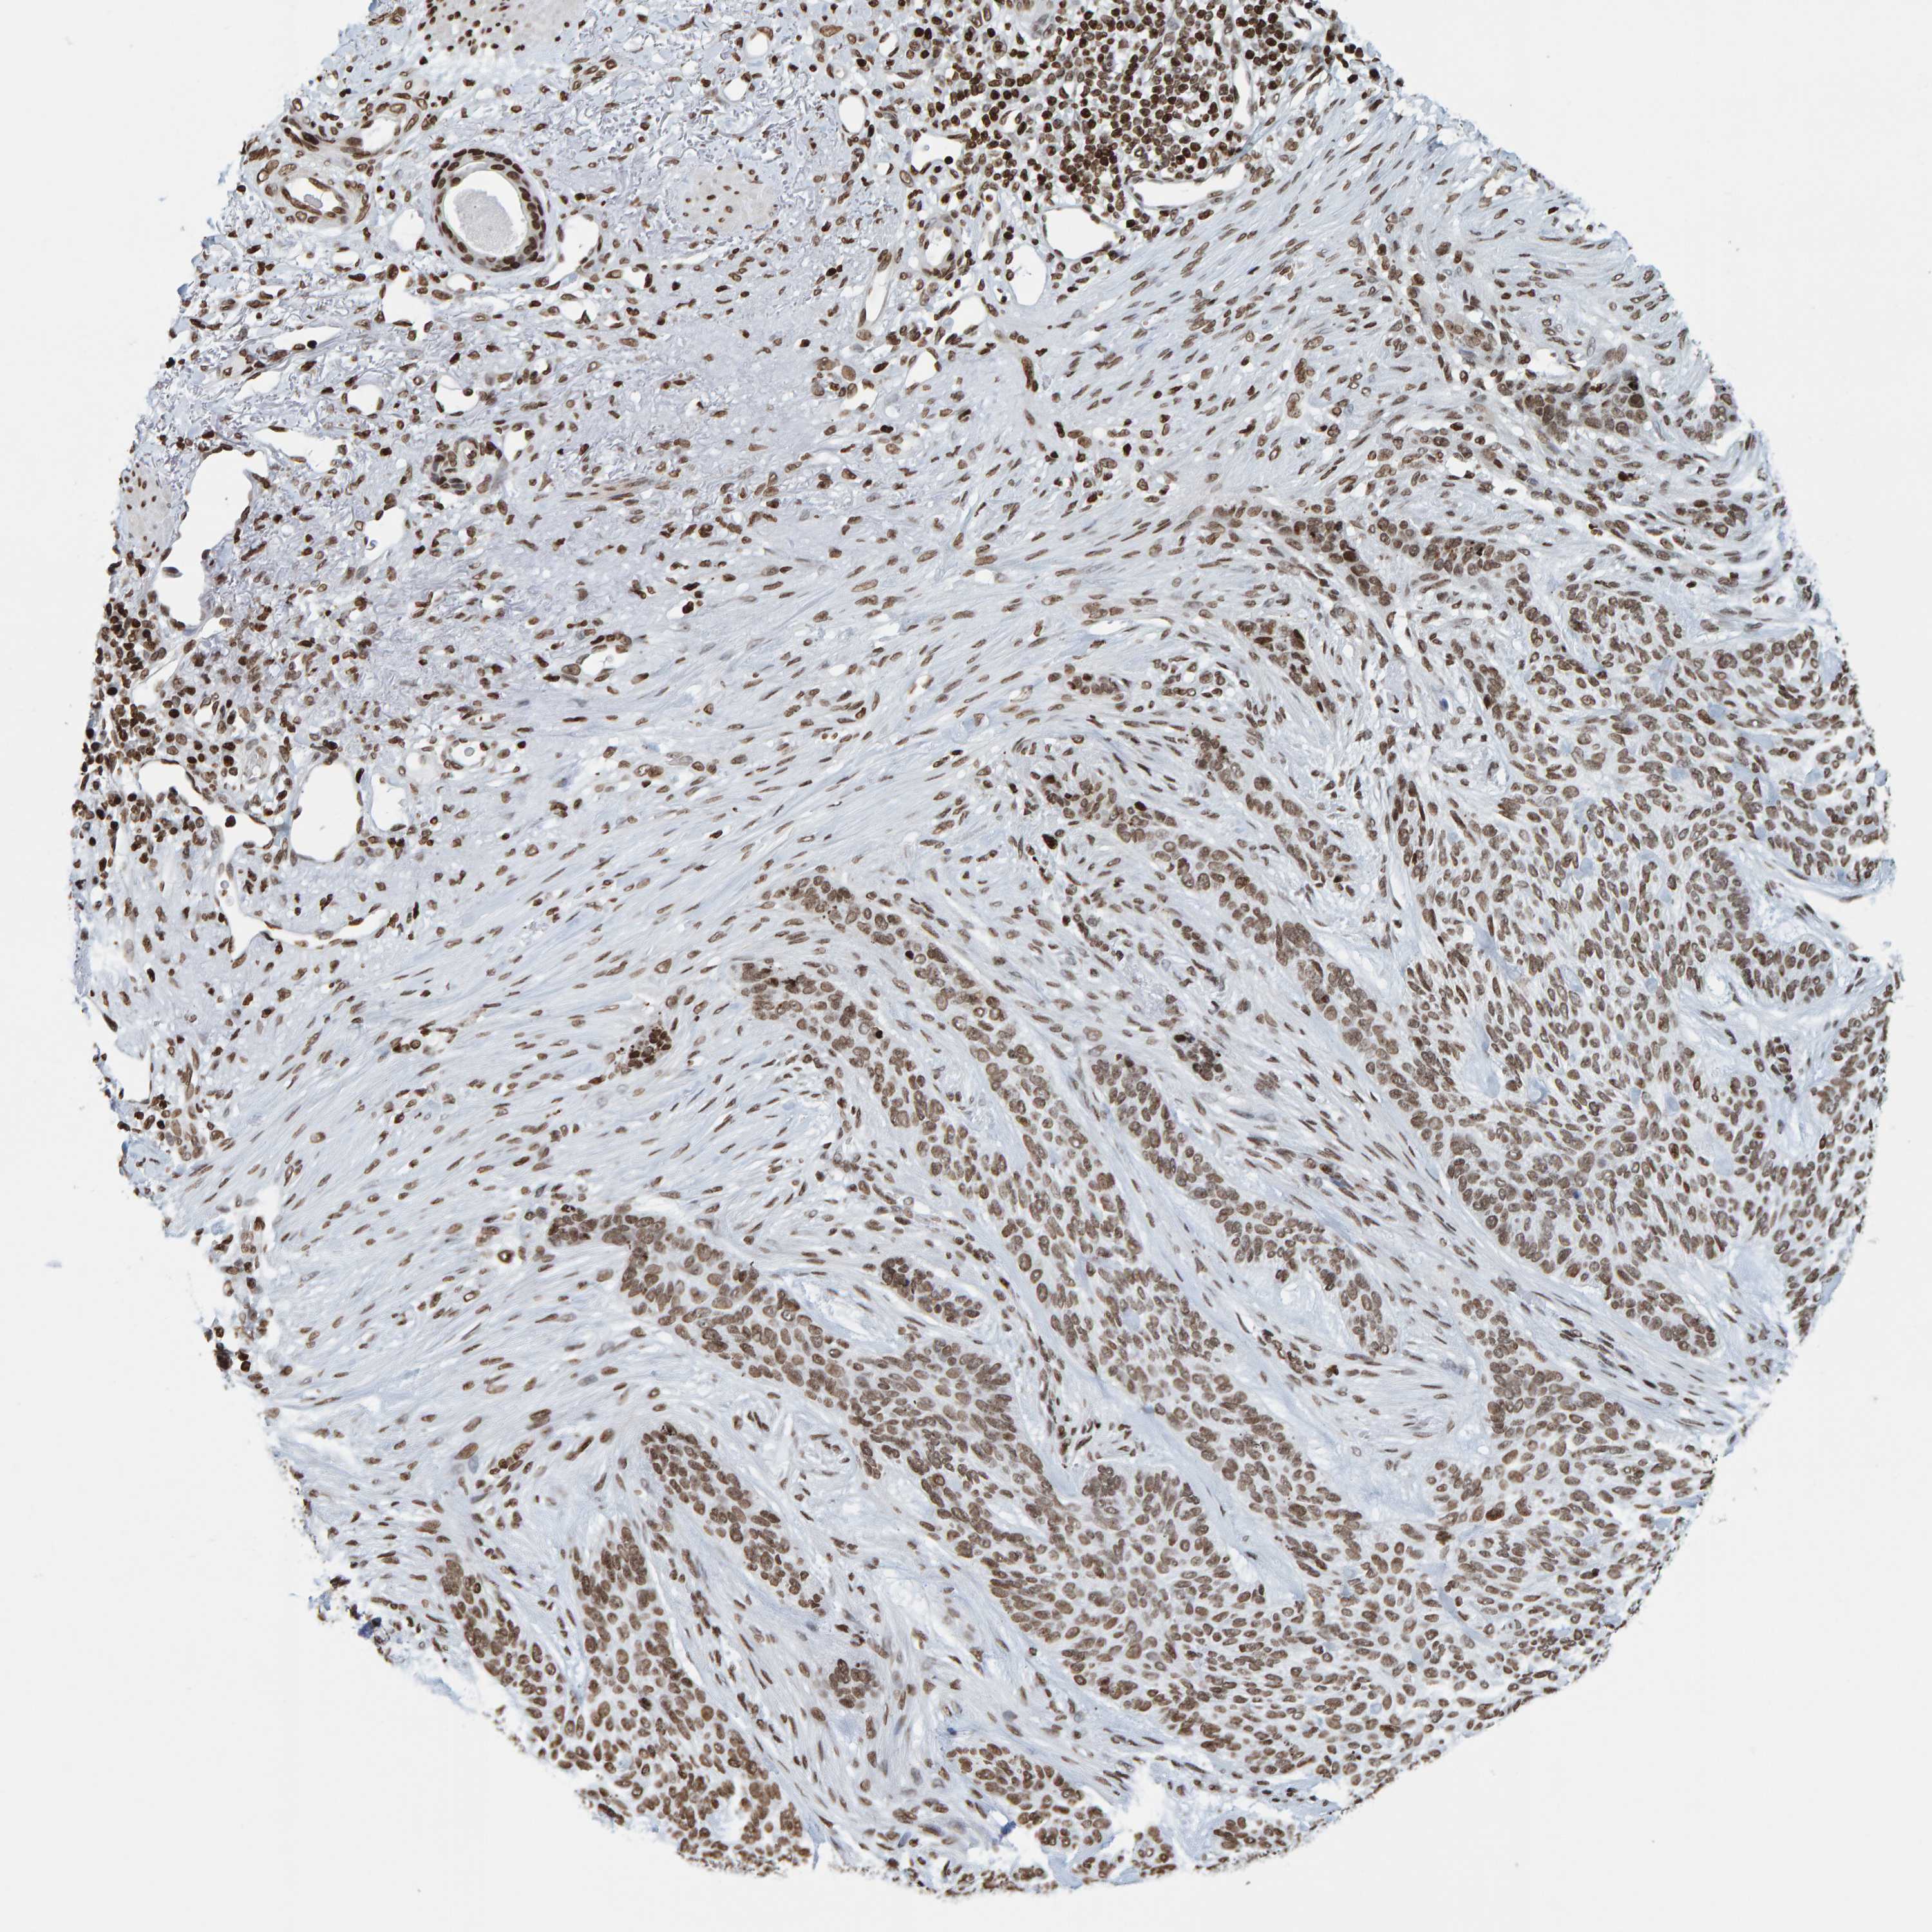

SKIN CANCER - Protein expressioni

A mouse-over function shows sample information and annotation data. Click on an image to view it in a full screen mode. Samples can be filtered based on level of antibody staining by selecting one or several of the following categories: high, medium, low and not detected. The assay and annotation is described here.

Antibody stainingi

Antibody staining in the annotated cell types in the current human tissue is reported as not detected, low, medium, or high, based on conventional immunohistochemistry profiling in selected tissues. This score is based on the combination of the staining intensity and fraction of stained cells.

Each image is clickable and will lead to virtual microscopy that enables deeper exploration of all samples and also displays staining intensity scores, fraction scores and subcellular localization as well as patient and tissue information for each sample.

Antibody CAB019269

Squamous cell carcinoma, NOS